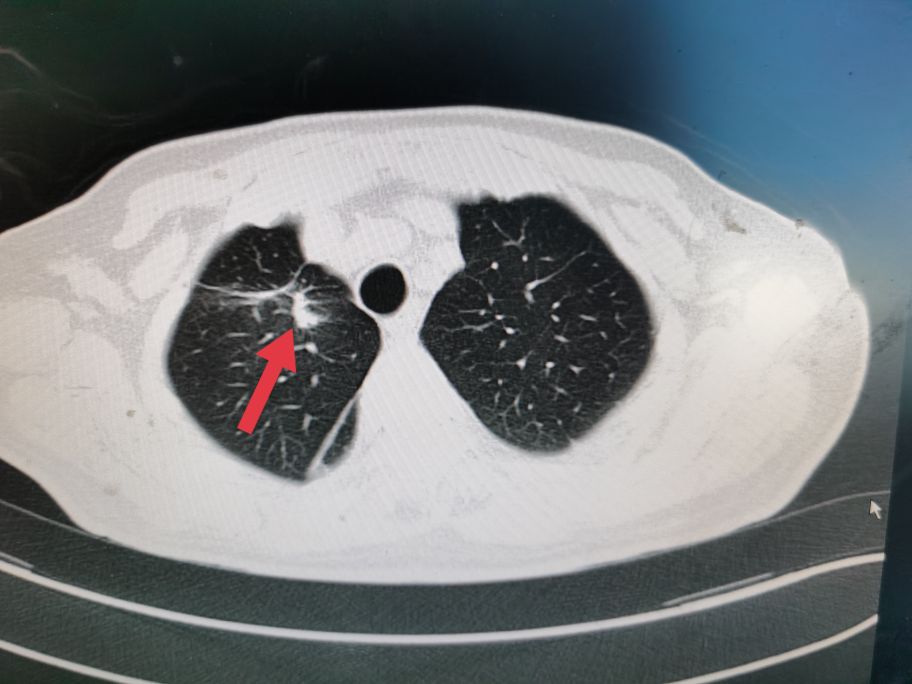

右肺部术后瘢痕

尽管病情危重,但王老非常坦然,好像把生死看的很淡,笑看人生总是尽力积极配合治疗。王老尽管年龄很大并且做过好几次手术,但是由于平时保养的不错,看上去偏年轻,并且住院后各种检查发现除心脏功能差一点,其它器官功能还可以。化验检查肿瘤标记物甲胎蛋白(AFP)特别高,超过9000ng/ml,考虑是种特殊类型的贲门癌,血色素63g/l,并且胃管里仍时有鲜血引出,腹部CT检查食管下段及贲门区占位,邻近淋巴结肿大,较上次检查明显增大,考虑为转移。因为病情重,连个增强CT都没敢做。